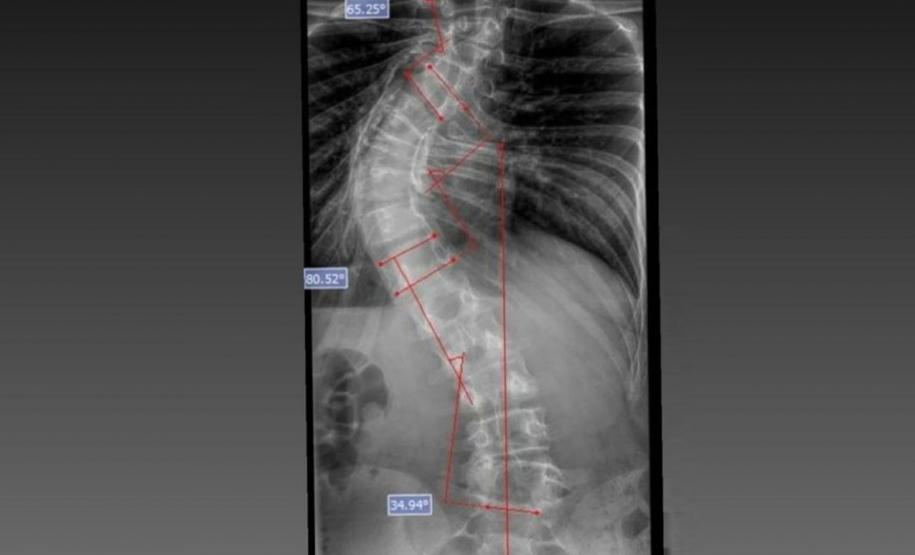

Laura era portadora de escoliose e, em agosto de 2025, realizou a cirurgia de correção da coluna, o que lhe permitirá ter uma vida normal de agora em diante. Moradora de Bom Sucesso do Sul, região Oeste do Paraná, é acostumada a andar a cavalo, mas com o problema na coluna a prática estava longe de ser prazerosa.

O médico João Elias explica que a escoliose é um termo usado para quando você olha a coluna e percebe uma curvatura. Pode acontecer por várias causas, desde uma escoliose congênita, quando o bebê nasce com uma vértebra mal formada e essa vértebra vai levando ao desenvolvimento de uma deformidade na coluna; a neuromuscular, causadas por doenças neurológicas ou musculares, como uma paralisia cerebral, até as idiopáticas, causadas por alterações genéticas e que podem se desenvolver apenas na adolescência.

Segundo ele, o verão é o período em que mais se diagnostica a doença. Por causa do uso de roupas mais leves, é mais fácil notar a alteração na coluna. Caso seja percebida alguma alteração, uma avaliação ortopédica deve ser marcada. “O diagnóstico precoce é importante. Quando a gente percebe que a coluna está iniciando uma curvatura é possível controlar essa curva. Fazer o procedimento com uma curvatura menor permite melhores resultados na cirurgia”, explicou.